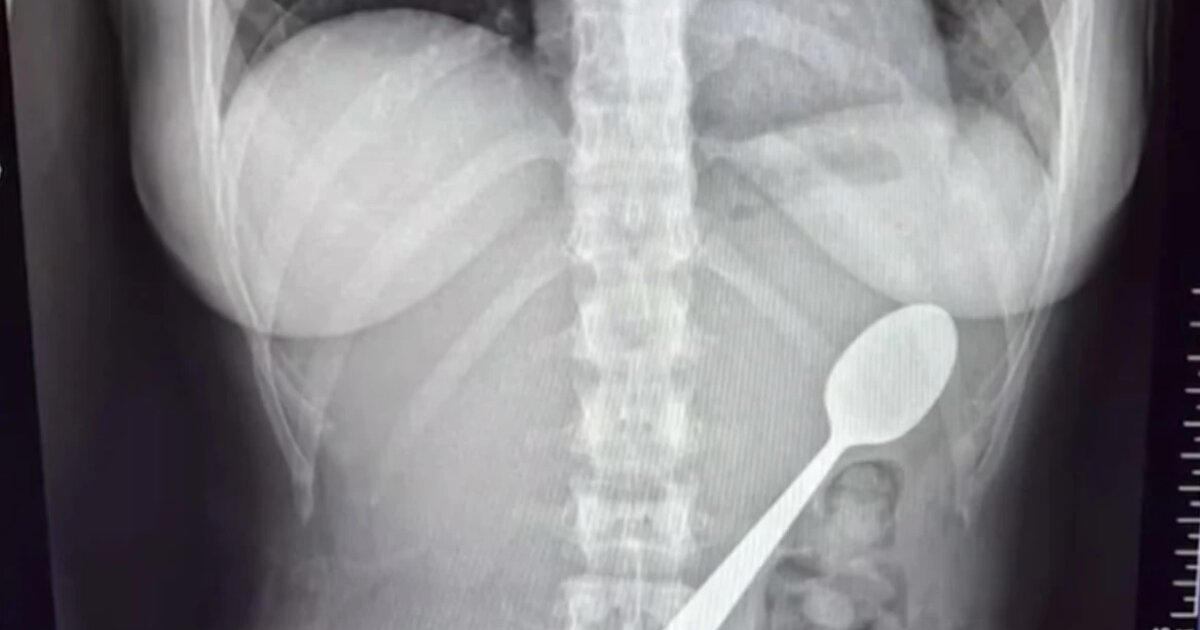

Αρχικά δεν ένιωσε έντονη δυσφορία και, όταν επέστρεψε ο σύντροφός της στο σπίτι, δεν του αποκάλυψε τι είχε συμβεί. Ωστόσο, μετά το δείπνο συνειδητοποίησε ότι το περιστατικό δεν μπορούσε να αγνοηθεί και απευθύνθηκε σε γιατρούς. Οι εξετάσεις έδειξαν ότι το κουτάλι ήταν πολύ μεγάλο για να αποβληθεί φυσιολογικά και αποφασίστηκε η αφαίρεσή του με γαστροσκόπηση.

Το διάστημα μέχρι την επέμβαση ήταν δύσκολο, καθώς, όπως ανέφερε, ένιωθε το κουτάλι να κινείται μέσα στο σώμα της, προκαλώντας φούσκωμα, ναυτία και έντονη δυσφορία. Δύο ημέρες αργότερα, οι γιατροί αφαίρεσαν το κουτάλι με ενδοσκοπική διαδικασία υπό αναισθησία. Κατά την επέμβαση χρειάστηκε να περιστραφεί μέσα στο στομάχι, προκαλώντας μικρή γαστρική αιμορραγία, ωστόσο η διαδικασία ολοκληρώθηκε με επιτυχία.